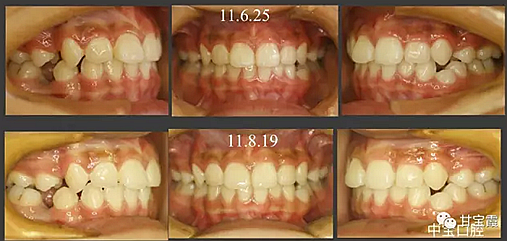

病例一

有一個七歲的小女孩,在替牙時媽媽發(fā)現(xiàn)孩子新長的牙不整齊,有一顆長到里面了,上下頜中線也不對稱,很著急就來到門診看牙。

經(jīng)過我臨床檢查和X線的診斷,決定早期干預,每三個月定期復診檢查一次,并拔掉了幾個乳牙和四個恒牙,正畸專業(yè)叫序列拔牙。

5.png

經(jīng)過三年零九個月的看護,最終戴上了固定矯治器,但是大家不難發(fā)現(xiàn),孩子的牙齒已經(jīng)排齊,上下中線也基本對齊,面型也好看多了,這樣矯正就變得簡單,療程自然縮短,孩子也不遭罪了。